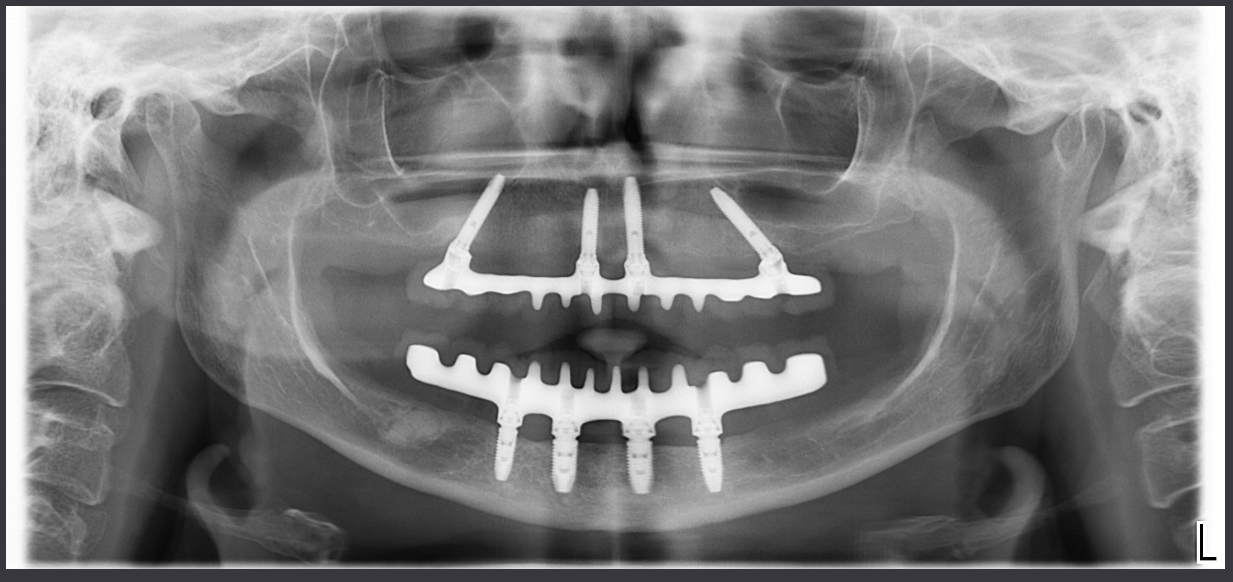

Questo è il controllo a un anno della mia paziente, un giorno ti mostrerò l’inferiore!

Eppure l’osso non c’era!!!! O almeno così aveva detto l’interpretazione rigida della simulazione al computer.

Come mai Rocco, pur avendo una capacità tecnica assolutamente paragonabile alla mia, non ha fatto lo stesso? Il suo caso era assoutamente analogo… anzi direi, più semplice di questo. Non mi faintendere, erano entrambi molto complessi… ?